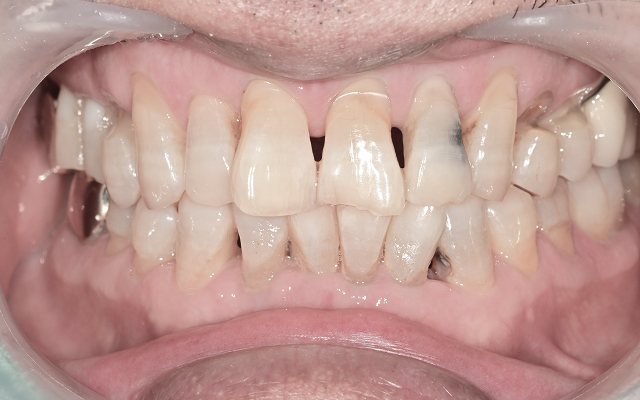

진료 전 구강 스캔과 구내 촬영을 통해

치아 상태를 꼼꼼하게 분석하고 설명드립니다.

엑스레이, 구강 사진, CT 등을 통해 꼼꼼히 진단하고 촬영한 사진을 함께 보며 쉽게 이해하실 수 있도록 설명드립니다.